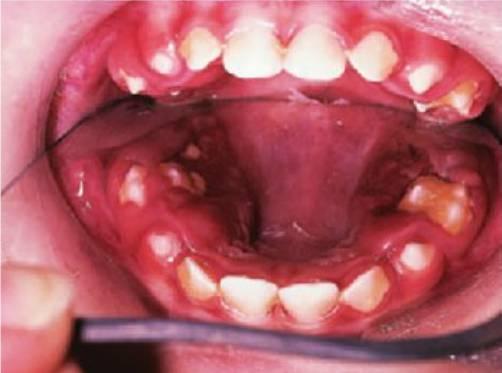

Ulceración de Riga-Fedé

Es una ulceración de la superficie ventral de la lengua causada por un traumatismo producido por los movimientos protrusivos y retrusivos continuos sobre los incisivos inferiores (fig. 8.5B). Se consideraba un hallazgo común en los casos de tos ferina; en la actualidad, se suele ver tan sólo en niños con parálisis cerebral.

Tratamiento

Pulir los bordes incisales agudos o colocar recubrimientos de resina composite sobre los dientes. En raras ocasiones se considerará la extracción de los dientes.